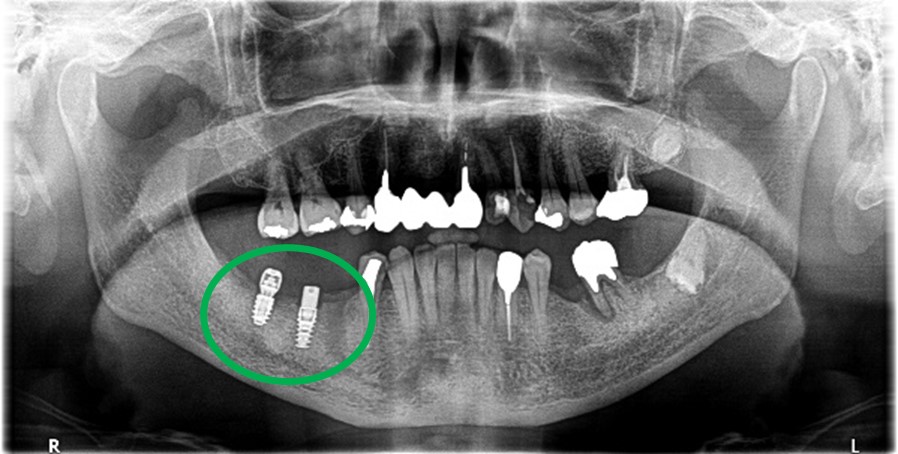

Before

※赤丸を抜歯しました。

After

歯根の周りの骨が全く無い状態でしたので、保存することができず抜歯しました。3本歯がないところに2本インプラントを埋入しました。

所感

抜歯後、歯がなくなったところを補う方法には、部分入れ歯とインプラントがあります。この症例の場合、右下以外ほとんど歯が残っていますので、もし部分入れ歯にした場合、入れ歯のところで他のところと同じ感覚で噛むことができないので、慣れることが大変です。また部分入れ歯の支えになっている歯に負担がかかりますので、今後さらに歯を失う可能性が大きくなります。インプラントは、自分の歯と同じ感覚で噛むことができ、単独で植立していますので他の歯に負担がかかることがありませんので、更に歯を失うことを防ぎます。